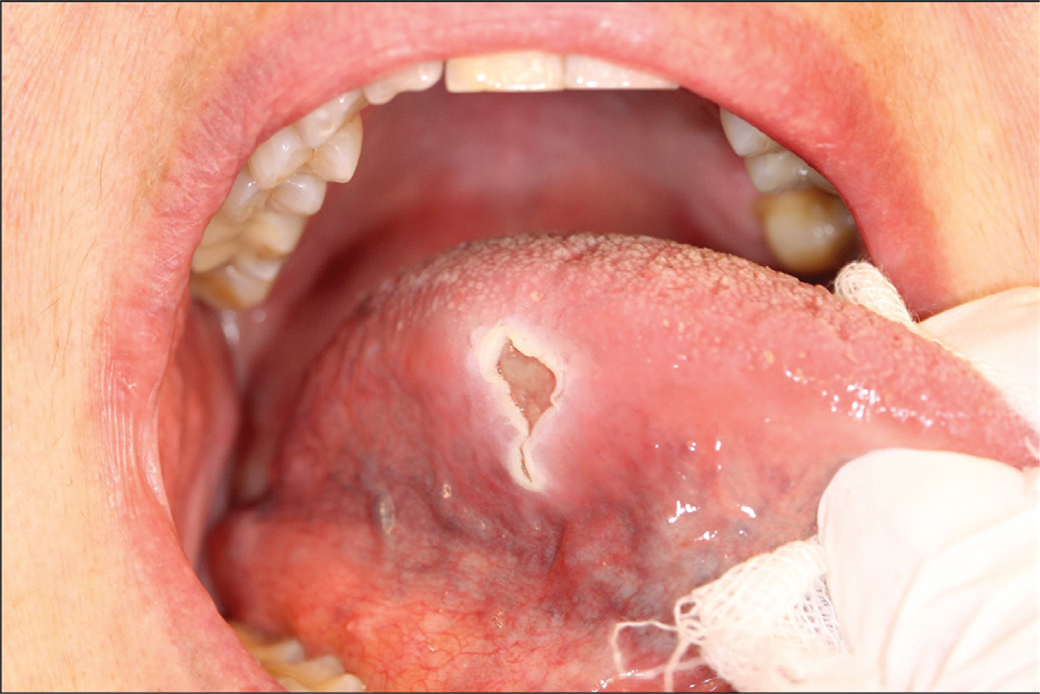

In December 2014, a 71-year-old woman was referred to the Department of Plastic and Oral and Maxillofacial surgery at Uppsala University from the Ear, Nose, and Throat Department (ENT). The reason stated for referral was a painful ulcer on the right side of the tongue, which had manifested 6 months earlier. The ulcer had a fibrinous base and was firm, but not indurated (Figure 1). There were no lymphadenopathies nor a history of fever. The patient was a non-user of tobacco but consumed moderate amounts of alcohol. She had a history of type 2 diabetes, hypertension, asthma, and osteoporosis. Intake of medications included Montelukast, Budesonide, Salbutamol, Prednisolone, Acetylcysteine, Omeprazole, Colestipol, Loperamide, Felodipine, Furosemide, Losartan, Zopiclone, and Alendronic acid. An incisional biopsy with histopathological examination (HPE) was conducted from the lateral border of the tongue. It displayed an inflamed tongue mucosa, with the epithelium being hyperplastic and hyperkeratinized. Blood tests showed C-reactive protein levels of 11 mg/L (< 5 mg/L) and a white blood cell count of 10.8 (3.5–9–109 cells/L). There were no signs of dysplasia, and malignancy could be ruled out. She received treatment with Clobetasol and Chlortetracycline with no improvement of the symptoms.

Fig 1

Figure 1. First visit in December 2014 showing a firm ulcer with a fibrinous base.